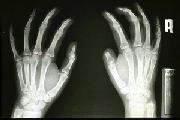

ตัวอย่างผู้ป่วยที่ทำ wrap around flap (รูปที่ 63-76)